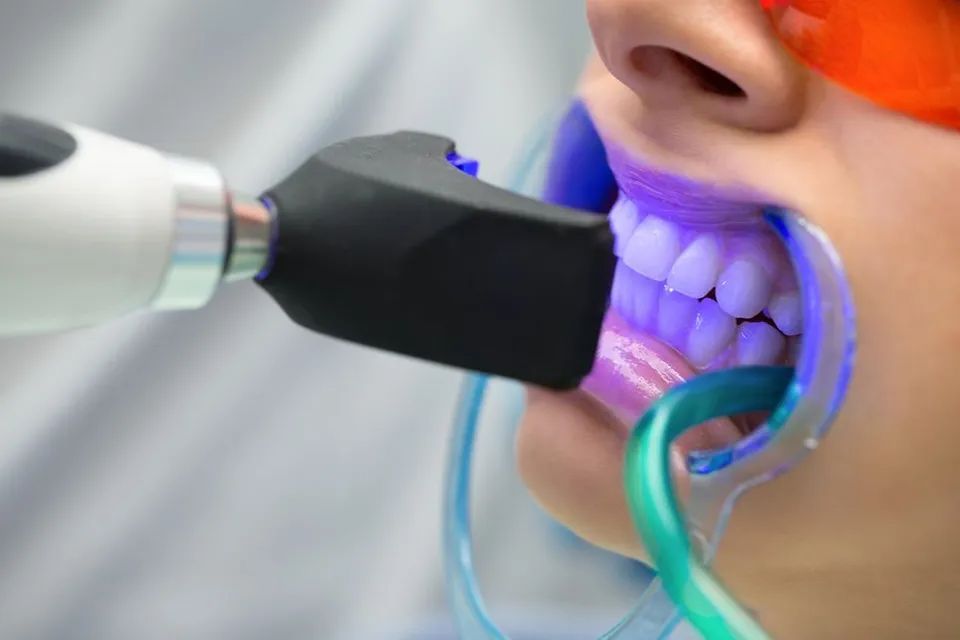

Lo studio offre le migliori soluzioni nel campo dell’odontoiatria ed è specializzato in implantologia garantendo interventi affidabili e sicuri. Igiene orale, chirurgia avanzata, ortodonzia per adulti e bambini, protesi fissa e mobile. Scoprite subito tutti i nostri servizi.